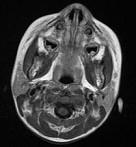

问题 女,13岁,皮肤有多发结节和多发棕色素斑,MR表现如图,最可能的诊断是()

选项 A.脸颜面血管瘤病 B.结节性硬化 C.神经纤维瘤病 D.听神经瘤 E.松果体瘤

答案 C